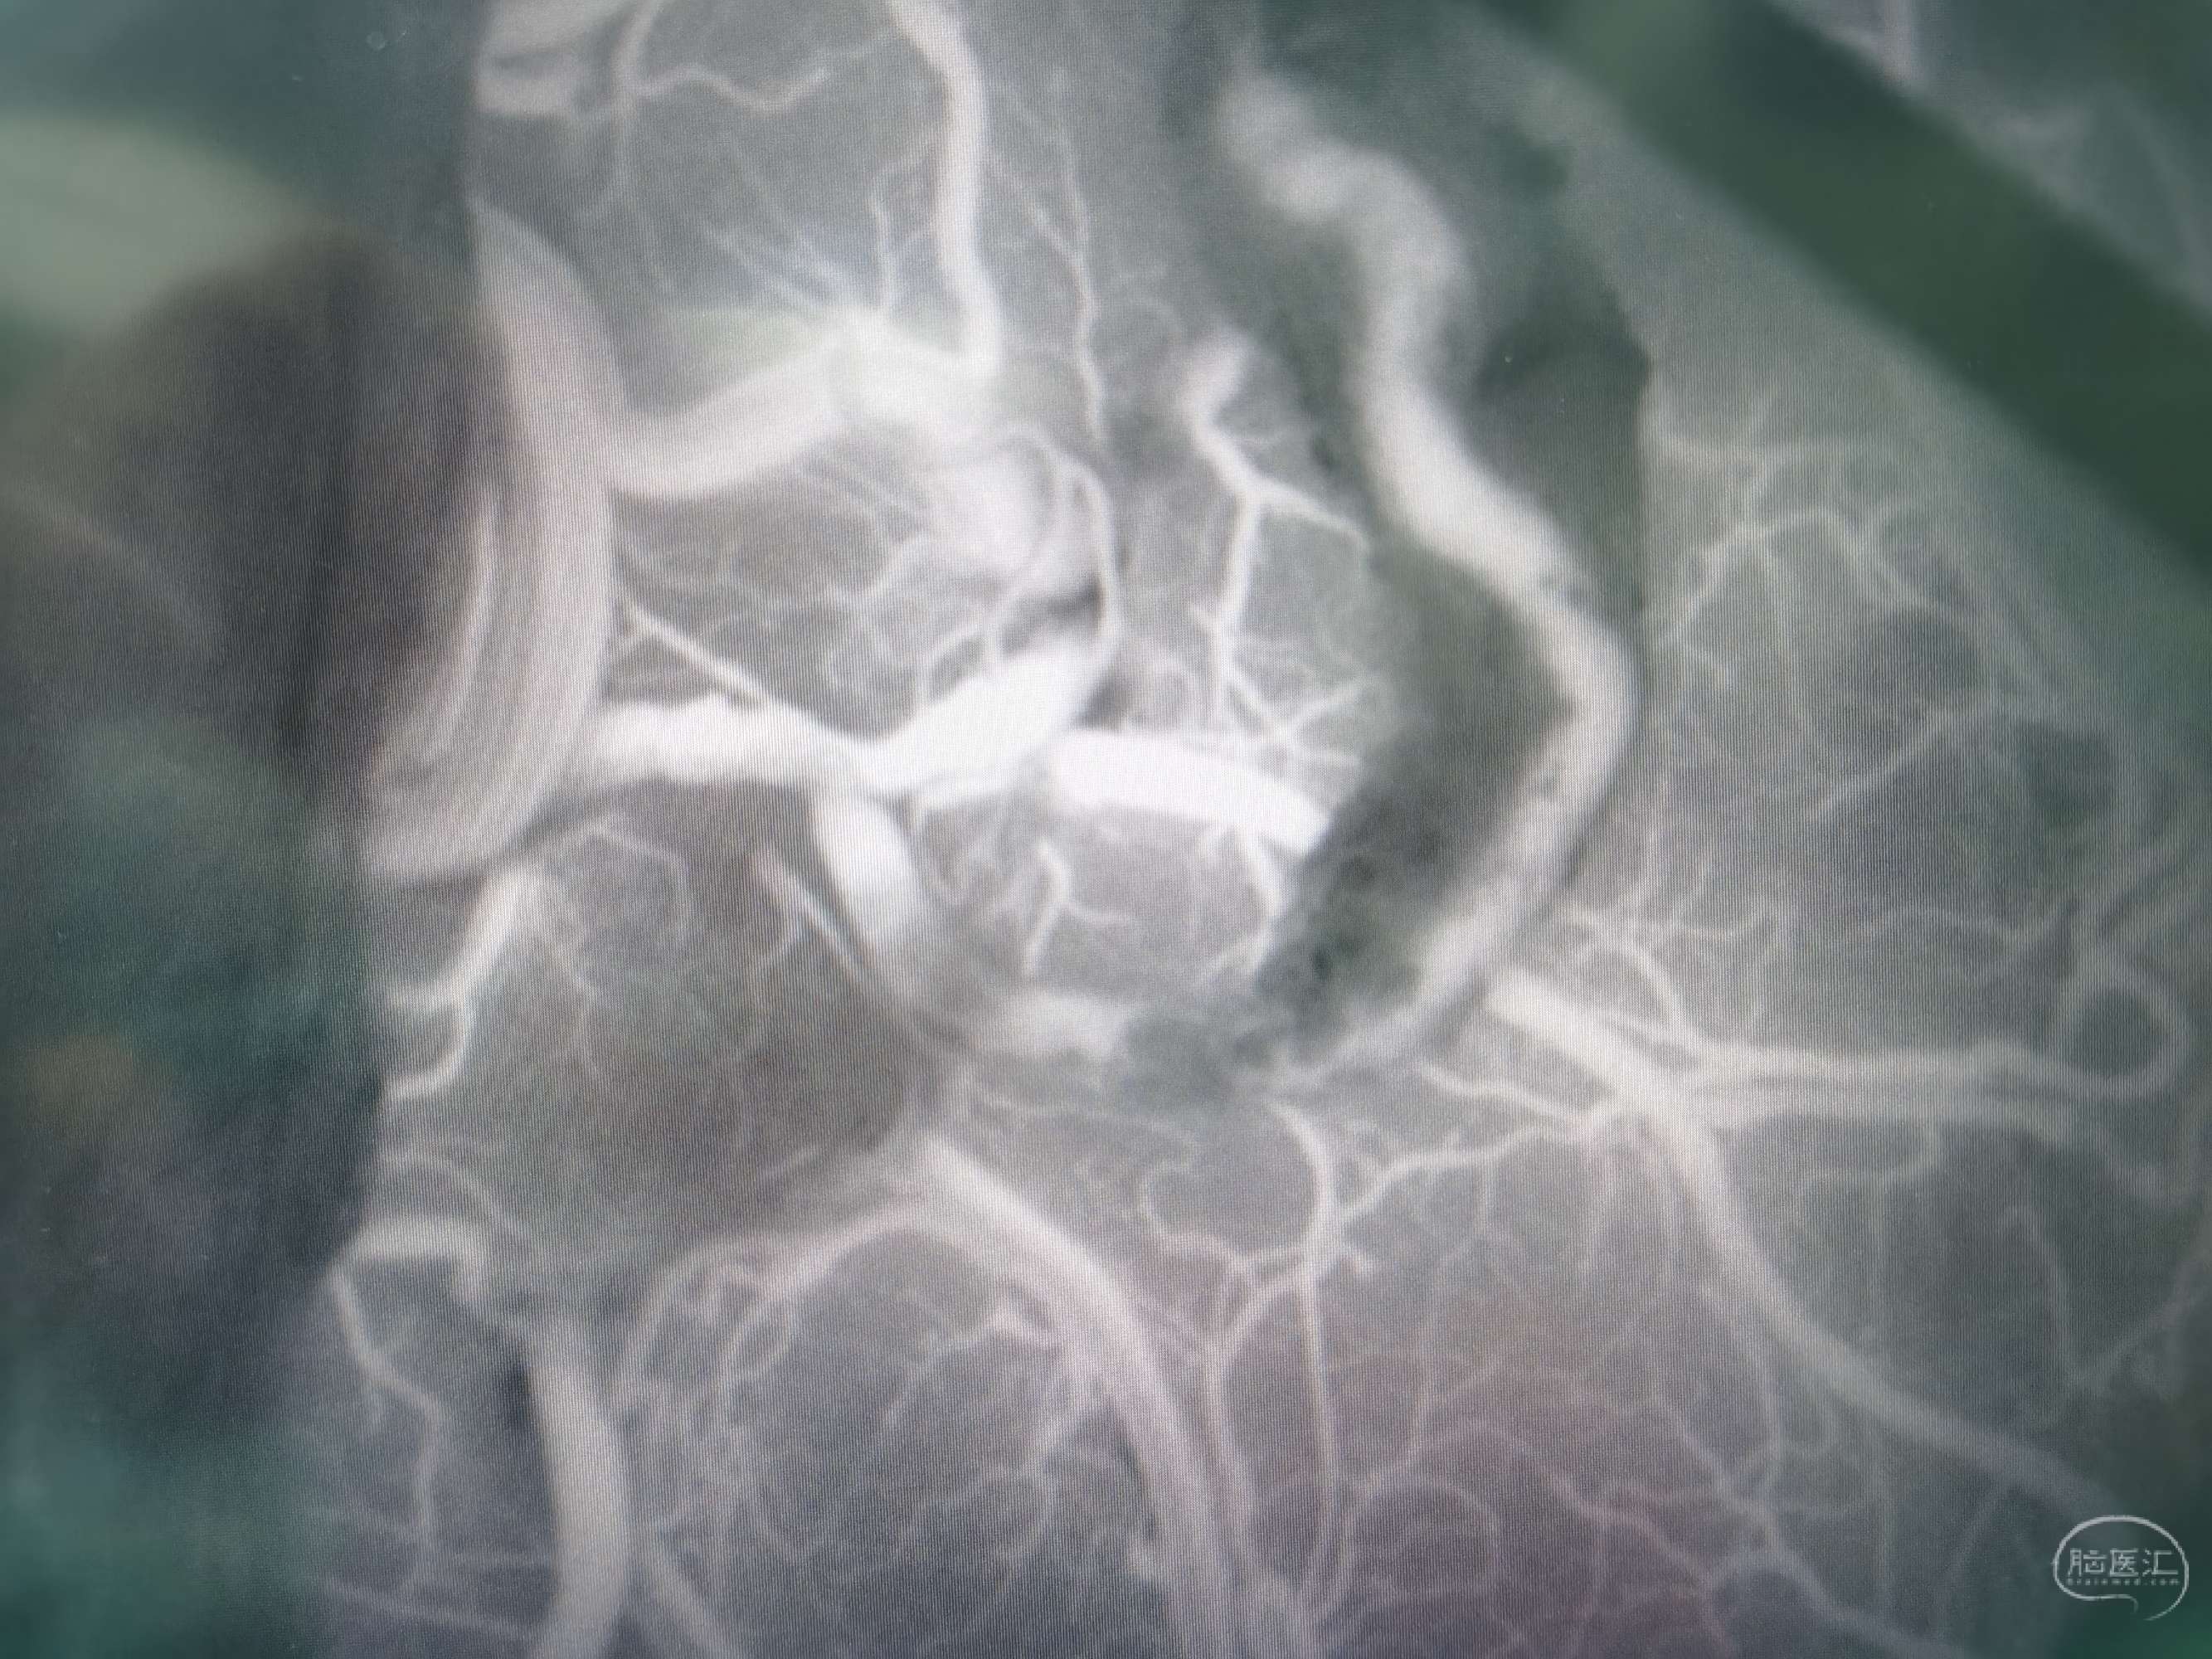

颞浅A-M4端侧吻合16针,荧光造影显示:吻合血管通畅。

颞浅A-M4端侧吻合14针,荧光造影显示:吻合血管通畅。